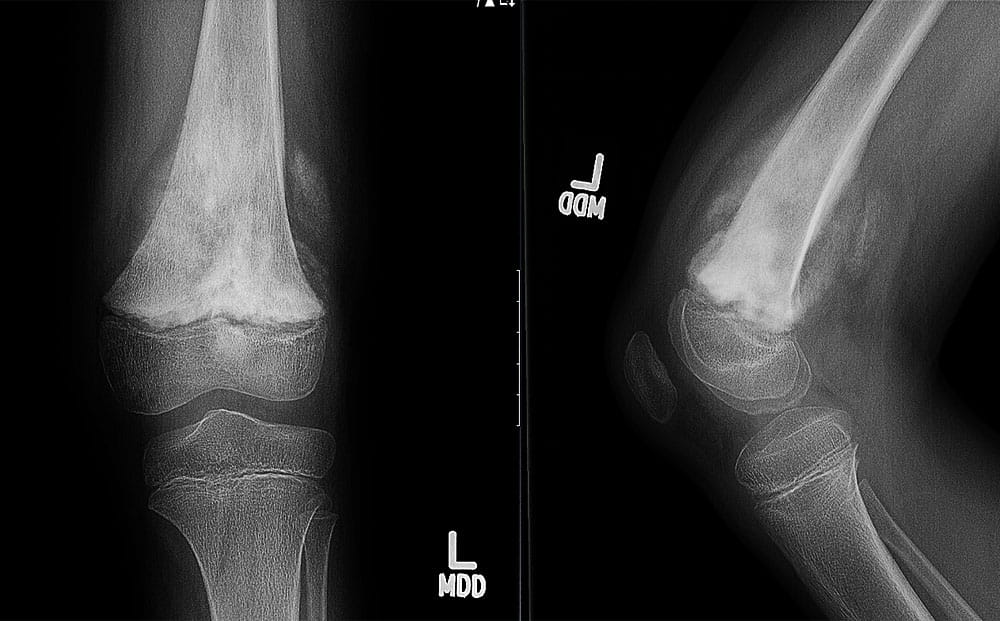

When a tumor of musculoskeletal tissue is cancerous, it is called sarcoma. It is the job of the orthopedic oncologist to diagnose these tumors and determine if they have spread.

In addition to sarcoma, orthopedic oncologist also treat lymphoma, multiple myeloma and metastatic cancers that come from other areas of the body such as the breast, lung, prostate, kidney and thyroid gland. Orthopedic oncologists are crucial contributors to the treatment plan for these patients as they can provide treatment options that have the potential to greatly improve quality of life. Orthopedic oncologists also treat non-cancerous tumors of the musculoskeletal system such as lipomas, neurovascular tumors, bone cysts, fibrous tumors and many others.

In patients with musculoskeletal tumors, surgical removal of the tumor will often be the first recommendation, followed by surgical reconstruction of the affected area to restore function. Additional treatments may include:

Your first visit with one of our orthopedic oncologists will be a fact-finding mission. You will be asked to bring or send ahead of time all previously obtained imaging results and laboratory work. This is so that our surgeons can review your record and piece together what has been done, the most likely diagnoses, and what needs to be done next. If you haven't already had them performed, you can expect the surgeon to order bloodwork, X-rays, CT and/or MRI scans and potentially, a biopsy.